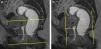

Las secuencias FSE T2 son útiles para evaluar posibles alteraciones musculares, como adelgazamiento o desgarros, en especial del músculo puborrectal (fig. 5). La serie axial debe planificarse en paralelo al propio puborrectal (línea H), desde el ano hasta un nivel superior al sigma. La serie coronal debe planificarse en perpendicular al puborrectal, desde la sínfisis púbica hasta el coxis (fig. 6).

Las secuencias dinámicas FIESTA se componen de múltiples imágenes de un mismo plano (multifase), obtenidas principalmente durante la realización de esfuerzos y cuya posterior visualización en sucesión rápida muestra el movimiento del contenido pélvico. Este tipo de secuencia permite obtener imágenes nítidas de las estructuras en movimiento, ya que cada imagen se obtiene en décimas de segundo (emplear la opción array spacial sensivity encoding technique [ASSET] contribuye a acelerar la adquisición). En nuestro protocolo obtenemos una serie coronal de 50 imágenes durante maniobra de Valsalva planificada sobre el canal rectal, útil para observar posibles rectoceles laterales (fig. 7). Obtenemos asimismo varias series de 120 imágenes de un plano sagital medio de la pelvis, centrado sobre el eje largo del canal rectal y cortando el cérvix (fig. 8). Es importante mantener esta orientación —salvo que el cérvix se encuentre desplazado lateralmente en exceso— para que este no quede fuera de plano y pueda visualizarse correctamente un posible descenso. Esta serie se realiza 4 veces: en reposo, con maniobra de contención, en maniobra de Valsalva y mientras el paciente tose. Finalmente, durante la evacuación, obtenemos una serie similar con 250 imágenes. Al tratarse de maniobras que conllevan presión abdominal, pretende observarse la respuesta del contenido pélvico ante tal presión. La serie adquirida durante la evacuación muestra además la función del músculo puborrectal, el recto y el canal anal. Si se produce una evacuación incompleta, es conveniente realizar una segunda serie. En el caso de las mujeres, puede valorarse si es necesario que la paciente realice una digitación intravaginal para favorecer la evacuación definitiva.